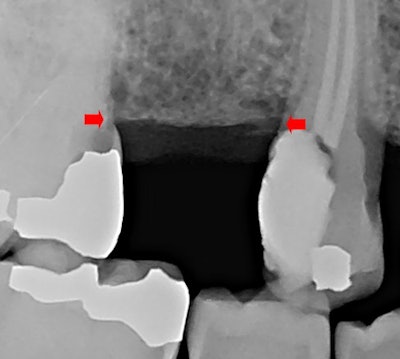

This case involved a healthy 73-year-old woman and her general dentist. She was deciding between two clinical treatments: an implant to replace tooth #4 or a fixed partial denture from teeth #3 and #5 with pontic #4. The patient was encouraged to obtain an implant instead of a fixed partial denture (bridge) because of longevity, especially with her caries susceptibility. Figure 1 shows the site with bone level indicated by red arrows.

There was inadequate tooth structure for restorations at #3 mesial and #5 distal because of decay near the crest of the alveolus.